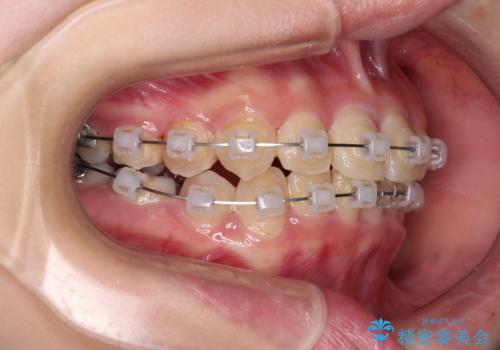

- クリアブラケット

- 犬歯のクロスバイトを気にして来院された患者様です。

マウスピース矯正とワイヤー矯正の両方を提案しましたが、インビザラインの自己管理が煩わしいとのことで、ワイヤー装置による矯正治療を行うこととしました。

犬歯は歯根が太くて長いため、クロスバイトを改善するのは大変であることが多いですが、比較的スムーズに改善することができました。

インビザラインであったら、もっと期間はかかっていたような印象です。